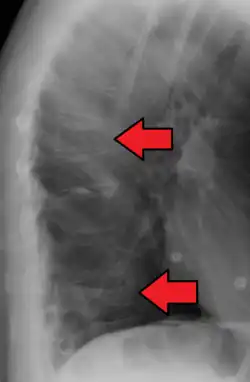

X-ray of the lumbar spine with a compression fracture of the third lumbar vertebra.

X-ray of the lumbar spine with a compression fracture of the third lumbar vertebra. -